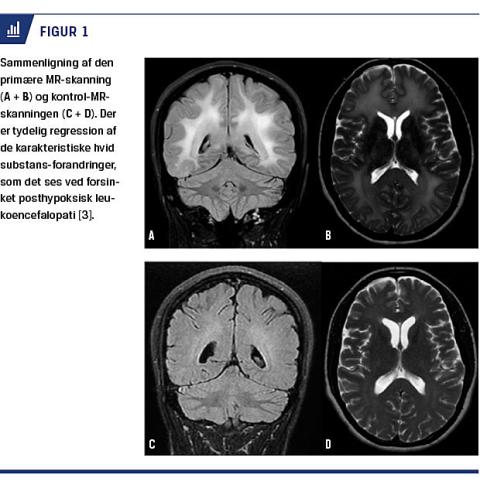

CT og lumbalpunktur, der blev foretaget inden for de første to døgn, viste normale forhold. Elektroencefalografi (EEG) foretaget ved indlæggelsen og gentaget efter to uger viste et encefalopatisk mønster. MR-skanning af hjernen viste svære symmetrisk fordelte højsignalforandring på T2 og fluid-attenuated inversion recovery i den supratentorielle hvide substans (Figur 1). På baggrund af patientens anamnese og de typiske MR-skanningsforandringer blev diagnosen DPHL stillet. Patienten blev på grund af kasuistiske meddelelser om mulig effekt [1] forsøgsvis sat i behandling med højdosisprednisolon i tre dage med langsom udtrapning til 0.

Der indtrådte en langsom bedring af symptomerne. Kontrol-MR-skanning af hjernen blev foretaget henholdsvis en og syv måneder efter den første skanning. Den første kontrolskanning viste let regression af forandringerne i den hvide substans, mens den anden kontrolskanning viste nærnormalisering af den hvide substans’ udseende (Figur 1). Ved ambulant kontrol otte måneder efter symptomdebut havde patienten lette kognitive deficit og søvnforstyrrelser, men markant bedring af både de fysiske og psykiske symptomer.